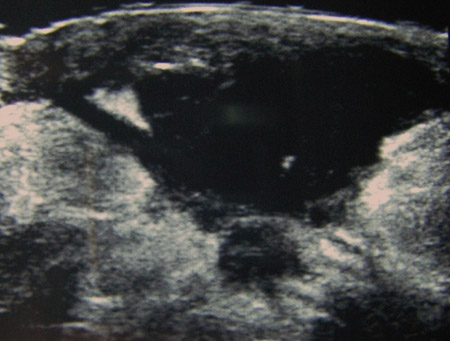

Ultrasound image showing a well-circumscribed hypoechoic breast abscess

From the collection of Holly S. Mason, MD, Tufts University School of Medicine, MA